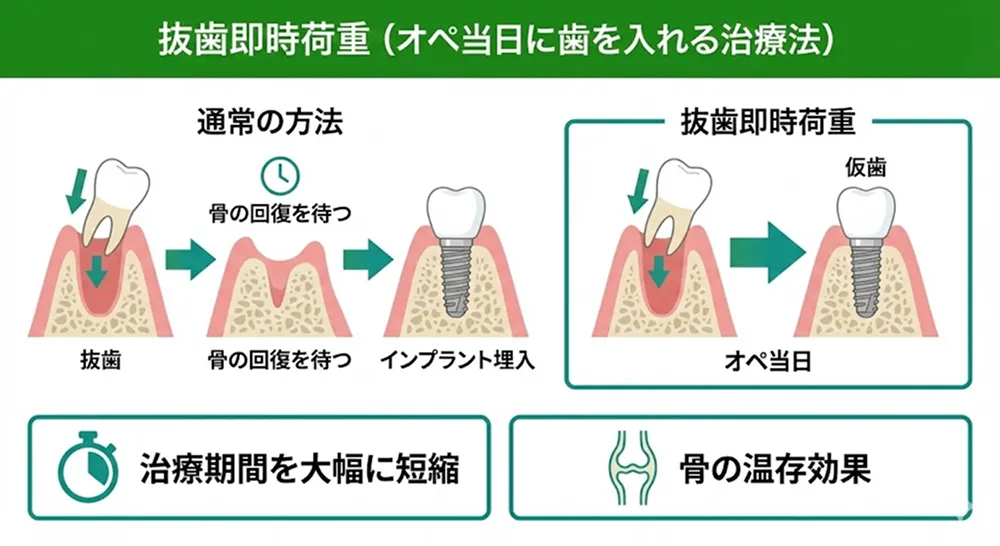

抜歯即時荷重(オペ当日に歯を入れる治療法)

抜歯即時荷重とは、抜歯と同時にインプラントを埋入し、その日のうちに仮歯を装着する術式です。

通常は抜歯後に骨が回復するのを待ってからインプラントを埋入しますが、この方法なら治療期間が短くなる可能性があります(適応には条件があります)。また、抜歯直後の骨を利用するため、骨の温存効果も期待できます。